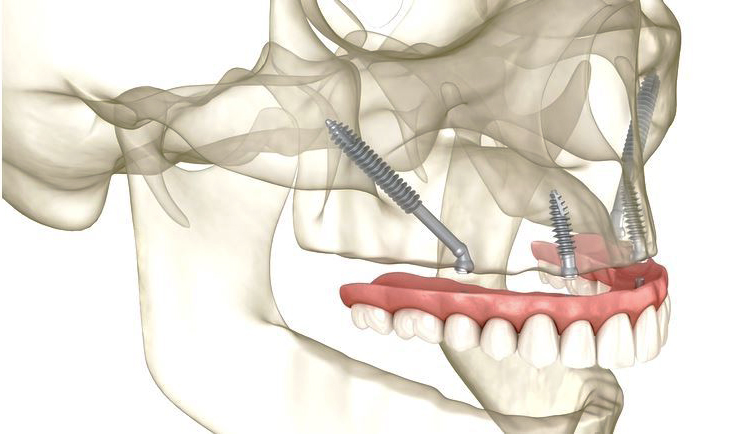

The surgical procedure for placing zygomatic implants is more complex than that of traditional implants, given the need to anchor into the zygoma.

Initially, a comprehensive pre-surgical evaluation, including imaging studies like CT scans, is performed to map out the anatomy and plan the implant placement.

On the day of surgery, the patient is typically placed under general anesthesia or conscious sedation for comfort.

The surgeon then makes an incision in the gum to expose the bone. A precise pathway is drilled from the alveolar crest to the zygoma, where the implant is anchored securely.

Due to the high density of the zygomatic bone, the implant achieves immediate stability, allowing for the placement of temporary prosthetics often on the same day.

Post-surgery, patients can expect some swelling and discomfort, which can be managed with prescribed medication. Follow-up visits are crucial to monitor the healing process and ensure successful osseointegration.